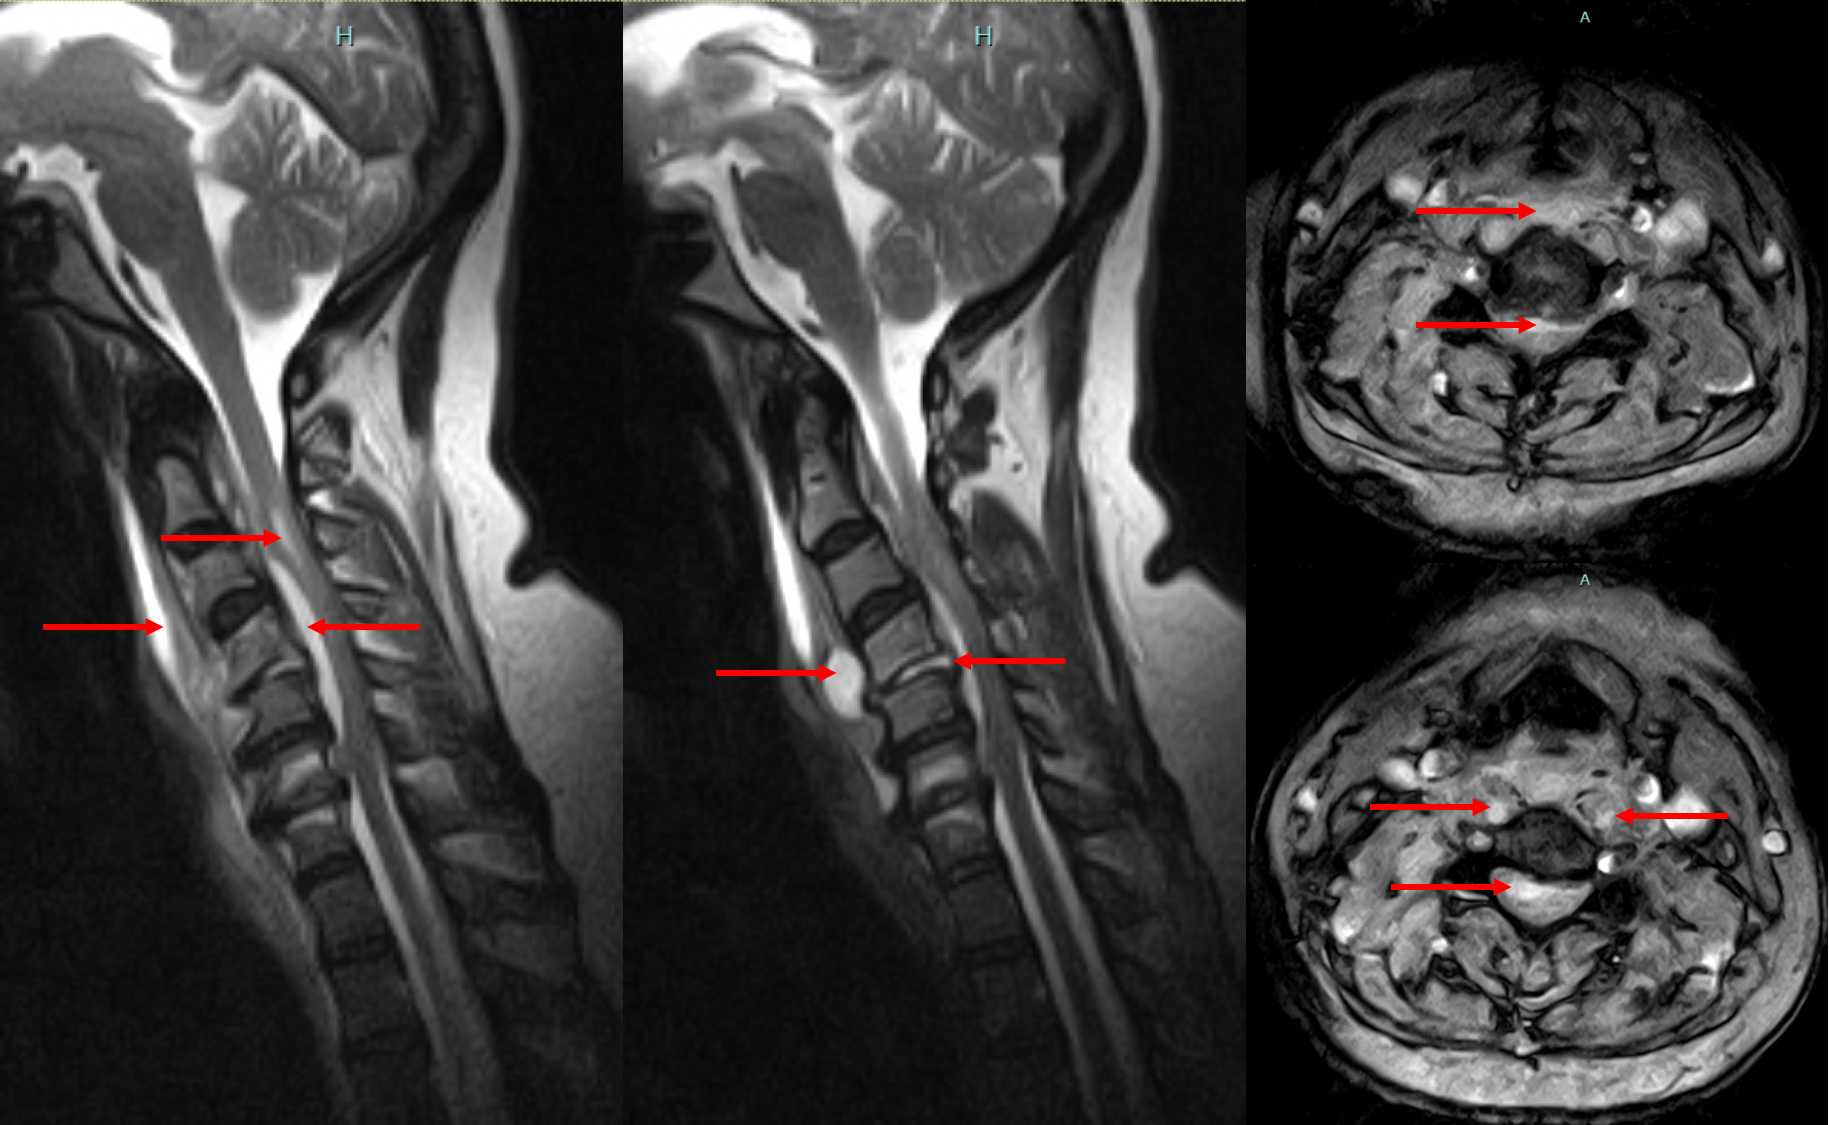

Comprehensive Diagnosis

Accurate diagnosis is the cornerstone of successful treatment. Our institute employs advanced diagnostic modalities to identify the cause, extent, and severity of spinal infections or tumours.

Diagnostic Tools Include:

MRI & CT Scans: To visualize soft tissues, nerves, and bone structures in detail.